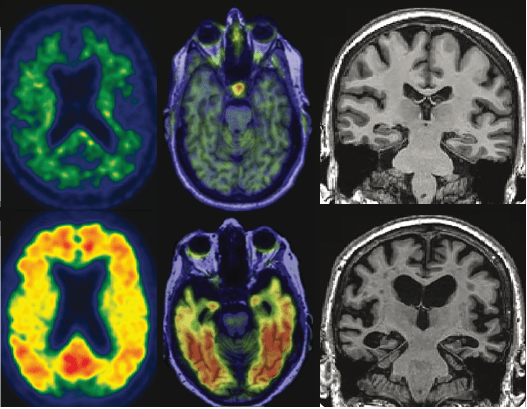

Examples of normal (top row) and abnormal (bottom row) amyloid, tau, and neurodegeneration as seen with PET and structural MRI

In the new framework, information about levels of amyloid (A) and tau (T) are used to stage patients along the AD continuum, while neurodegeneration (N) is used to stage disease severity. Each biomarker (the indicator of amyloid, tau, or neurodegeneration) is binarized into either positive or negative, leading to eight AT(N) biomarker profiles. Essentially, the presence of multiple abnormal (positive) biomarkers is indicative of more advanced disease.

In AD, researchers have yet to agree on how to standardize the methods of assessing the extent of pathology or how to determine if an individual is positive or negative on a given test result. Let’s use amyloid as an example. Amyloid can be measured with PET imaging as shown above, but it can also be measured in cerebrospinal fluid (CSF), the water-like liquid that bathes the central nervous system, which can be sampled with a spinal tap. Within either method, there are additional choices (there’s no standard way to measure amyloid in the CSF or kind of PET to use (PiB? Florbetapir? Florbetaben?)), including where and how to set the cutoff for being considered positive or negative for amyloid. Such tests haven’t even been validated outside of the largely white, wealthy, and well-educated subjects who make up most research cohorts, meaning the cutoffs we currently have may not apply to the majority of people anyway. To complicate things more, these two methods don’t actually measure the same thing. CSF is more like a snapshot in time of the current state, whereas PET shows the accumulated amyloid up until this point. And then there’s the issue that both CSF and PET measures estimate a certain form of amyloid (the fibrils, or aggregates of stuck together proteins which accumulate in plaques) when it’s thought that a different, soluble form of amyloid may actually be the toxic kind.